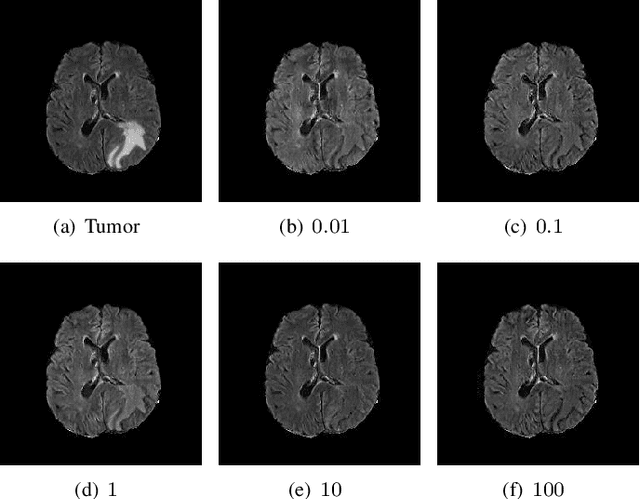

Abstract:The analysis of lesion within medical image data is desirable for efficient disease diagnosis, treatment and prognosis. The common lesion analysis tasks like segmentation and classification are mainly based on supervised learning with well-paired image-level or voxel-level labels. However, labeling the lesion in medical images is laborious requiring highly specialized knowledge. Inspired by the fact that radiologists make diagnoses based on expert knowledge on "healthiness" and "unhealthiness" developed from extensive experience, we propose an medical image synthesis model named abnormal-to-normal translation generative adversarial network (ANT-GAN) to predict a normal-looking medical image based on its abnormal-looking counterpart without the need of paired data for training. Unlike typical GANs, whose aim is to generate realistic samples with variations, our more restrictive model aims at producing the underlying normal-looking image corresponding to an image containing lesions, and thus requires a specialized design. With an ability to segment normal from abnormal tissue, our model is able to generate a highly realistic lesion-free medical image based on its true lesion-containing counterpart. Being able to provide a "normal" version of a medical image (possibly the same image if there is no illness) is not only an intriguing topic, but also can serve as a pre-processing and provide useful side information for medical imaging tasks like lesion segmentation or classification validated by our experiments.